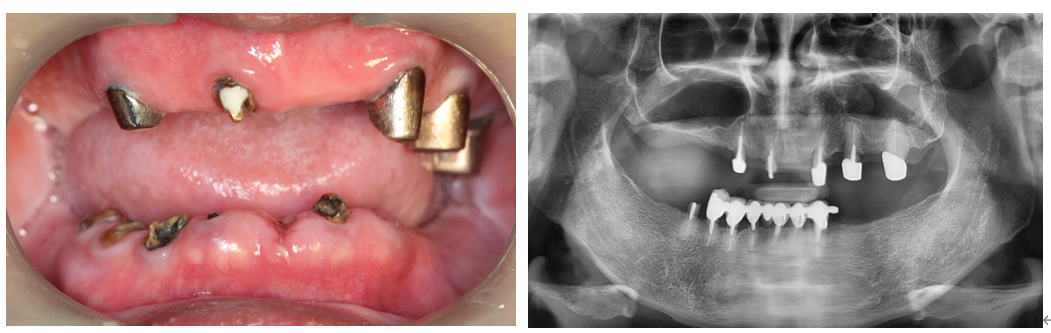

全口重建

70歲王老先生3年前求診,主訴:下顎假牙斷裂

科技植牙導航3D模擬

植體支撐式固定假牙完成,患者非常滿意外觀及咀嚼功能